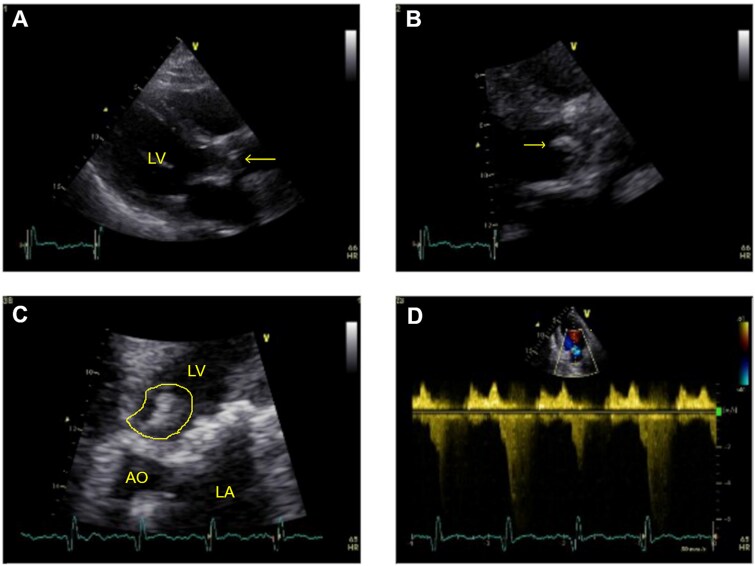

Case presentation: A 77-year-old man with a bioprosthetic aortic valve and pacemaker presented with two months of fever. He had a history of HLA-B27-negative ankylosing spondylitis treated with adalimumab. Examination revealed a systolic aortic murmur. Transthoracic echocardiography revealed vegetation on the aortic bioprosthetis. Serologies and cultures were negative. He underwent valve replacement, endocavitary pacemaker system removal, and epicardial pacemaker implantation. Valve tissue PCR and 16S rRNA sequencing were positive for T. whipplei. Empiric ceftriaxone was given for two weeks, followed by doxycycline and hydroxychloroquine for 12 months, then lifelong doxycycline monotherapy.